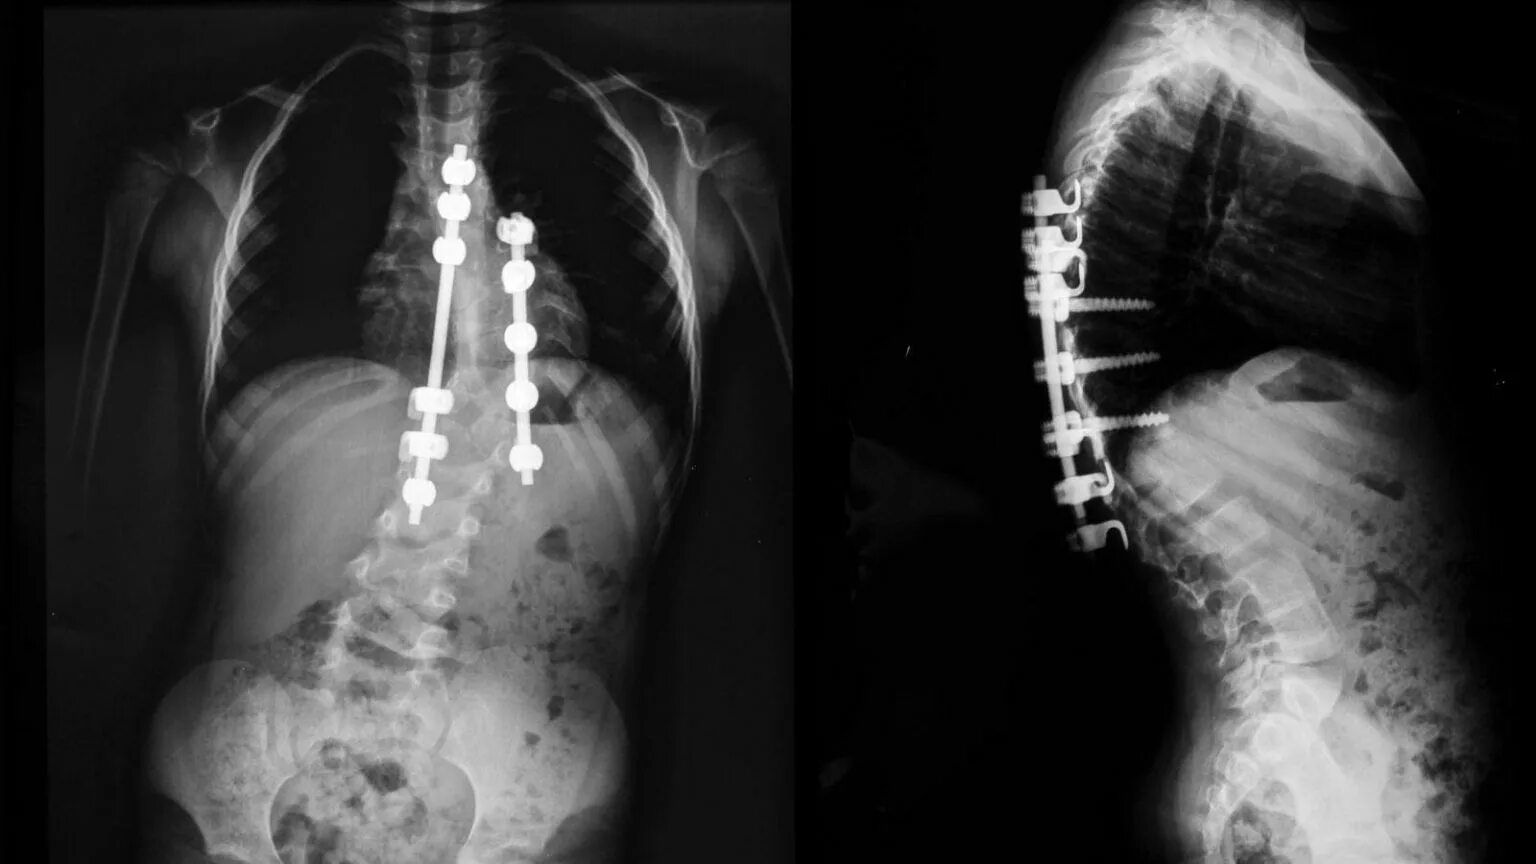

Сколиоз хирургия